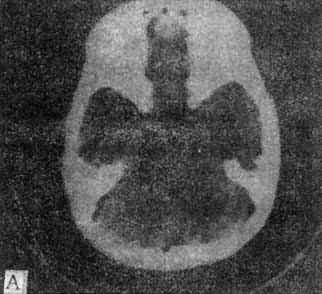

10mm底颅层面 此层面通过眦耳线上方10mm,由前向后可见眼眶上部、蝶窦和中颅凹底、枕骨及枕大孔等颅底结核。20mm蝶鞍层面 可见垂体、四脑室、桥池和桥小脑角池、岩锥与内耳道、前、中和后颅凹脑组织结构。本层面重点观察垂体和后颅凹结构。(图5-1-4A)。30mm鞍上池层面 可见鞍上池呈六角星或五角星形低密度脑脊液间隙,增强CT扫描尚可见脑底动脉环在池内的分布情形(图5-1-4B)。鞍上池后方、环池和四叠体池包绕部分即为中脑。40mm三脑室前部层面 重点观察内囊、基底节和丘脑区(图5-1-4C)。50mm三脑室后部层面除显示内囊、基底节和丘脑区外,同时是观察三脑室后部松果体区重点扫描层面(图5-1-4D)。60mm侧脑室体层面可观察侧脑室体部、三角区和后角(图5-1-4E);增强CT尚可见直窦、上矢状窦和大脑镰强化显影。70mm侧脑室顶层面 可见侧脑室顶部、大脑纵裂、脑皮质和脑髓质(图5-1-4F)。80~100mm脑室上层面 脑皮、髓质、脑沟和大脑纵裂清楚显示。

图5-1-4 正常头部CT扫描

A、蝶鞍一鞍上池层面,鞍上池和后颅凹同时显示,

B、鞍上池层面增强扫描,可见颅底动脉环显形